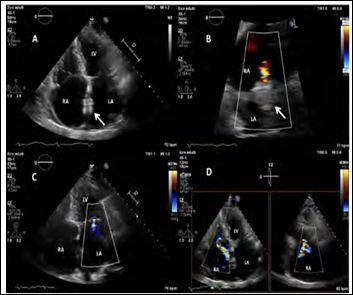

The Atrial Flow Regulator (AFR) device (Occlutech, Helsingborg, Sweden) (Figures 2A and 2B, Supplementary Table 1) with an 8-mm fenestration, 5-mm height and 21-mm discs diameter was implanted into the interatrial septum (Figure 3). Postoperative TEE showed left-to-right interatrial shunting through the device (Figure 4), significantly reduced mitral annular area and trivial residual mitral regurgitation (Figure 5). Post-procedural right heart catheterization demonstrated a drop in PCWP (12 mmHg), an increase in RA and a 1.2 QP/QS ratio (Table 1). At 3-months follow-up the patient was asymptomatic (NYHA I), BNP decreased to 380 ng/L and the 6MWT distance increased to 470 m. TTE showed AFR patency, mild mitral regurgitation (Figure 6, Supplementary Movie 1, B), moderate tricuspid regurgitation with mildly enlarged but normally functioning right ventricle.

Figure 6: TTE at 3-month-follow-up. The apical four-chambers A) and subcostal B) views confirm the stable position of the device (white arrow) with persisting left-toright shunt. The apical four-chamber C) and biplanar D) views demonstrate mild mitral and moderate tricuspid regurgitation.

Note: RA: Right Atrium; LA: Left Atrium; LV: Left Ventricle